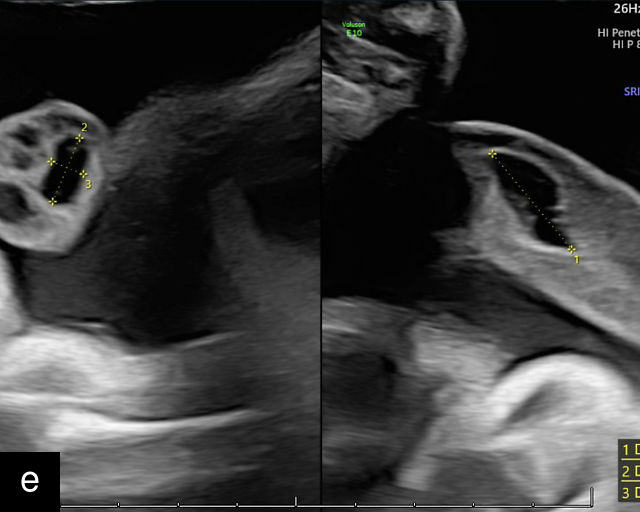

21

(a) Type-1 vasa previa. Photograph after delivery showing the umbilical cord inserting into the membranes through which unprotected fetal vessels run to insert into the placental edge. (b) Type-2 vasa previa. Photograph after delivery showing bilobed placenta with unprotected fetal vessels running though the membranes between the lobes. (c) Type-3 vasa previa in a twin pregnancy. Photograph after delivery showing unprotected vessels running through the membranes from one edge of the placenta to another (arrow). (d) Transabdominal grayscale ultrasound of the lower uterine segment showing a linear hypoechoic structure (fetal vessel) running over the cervix (c) indicating vasa previa (Type 2). b, bladder; h, fetal head. (e) Transabdominal color Doppler ultrasound of the lower uterine segment showing fetal vessels (arrow) running over the cervix (c) indicating vasa previa (Type 2). (f) Transabdominal ultrasound with color flow and pulsed-wave Doppler of the lower uterine segment showing a fetal vessel running over the cervix (c) indicating vasa previa (Type 2). Pulsed-wave Doppler demonstrates an umbilical arterial waveform. (g) Transvaginal grayscale ultrasound with showing a Type-2 vasa previa. There are two placental lobes, an anterior (a) and a posterior (p) lobe. There is a linear and circular hypoechoic structure (arrow) running over the cervix (c) between the lobes. (h) Transvaginal grayscale ultrasound image of vasa previa. A hypoechoic linear structure (arrow) is seen running through the membranes over the cervix (c). h, fetal head. (i) Transvaginal grayscale ultrasound of vasa previa. Hypoechoic circular and linear structures are seen close to the internal os. (j) Transvaginal color Doppler ultrasound image of vasa previa. A fetal vessel is seen running through the membranes over the internal os (arrow) of the cervix (c). h, fetal head. (k) Transvaginal ultrasound with color Doppler showing a Type-2 vasa previa. There are two placental lobes, an anterior and posterior lobe (pl). Fetal vessels run over the cervix between the lobes. (l) Transvaginal color flow ultrasound with pulsed-wave Doppler image of vasa previa. Color Doppler shows flow through the vessel and pulsed-wave Doppler shows a fetal umbilical venous waveform. (m) Transvaginal color ultrasound with pulsed-wave Doppler image of vasa previa. Color flow Doppler shows flow through the vessel and pulsed-wave Doppler shows a fetal umbilical arterial waveform. (n) Transvaginal three-dimensional ultrasound with color Doppler image of vasa previa. h, fetal head; c, cervix.

12